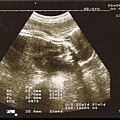

看大肚婆今天穿什麼﹝10月更新﹞